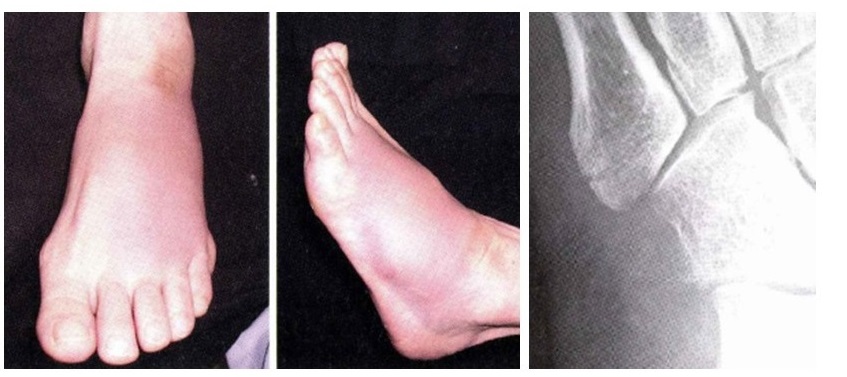

上の写真は、第五中足骨という足の甲の骨を骨折した患者の状態を示しています。足の甲、特に小指側が赤く腫れあがっているのが目に見えて分かるかと思います。

また、骨折時には骨が変形している事もあります。